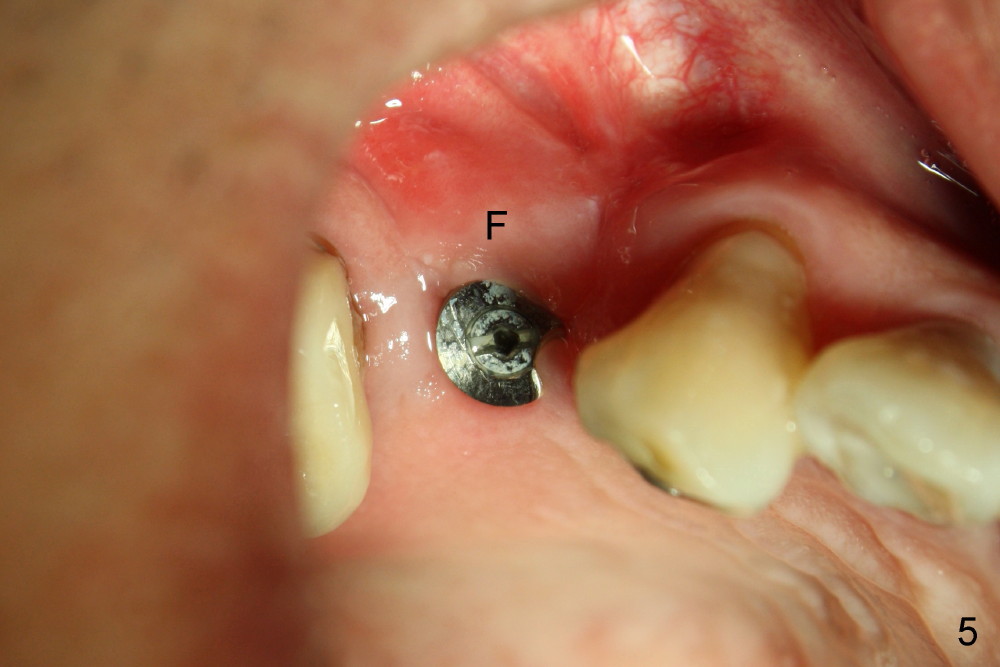

The flap (F in Fig.5, taken 2.5 months postop) is closed following the periosteum being underscored.